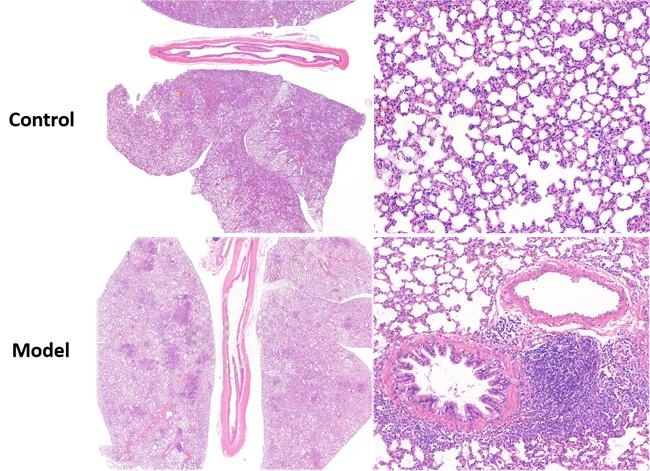

3、HE染色-肺

- 文献和实验